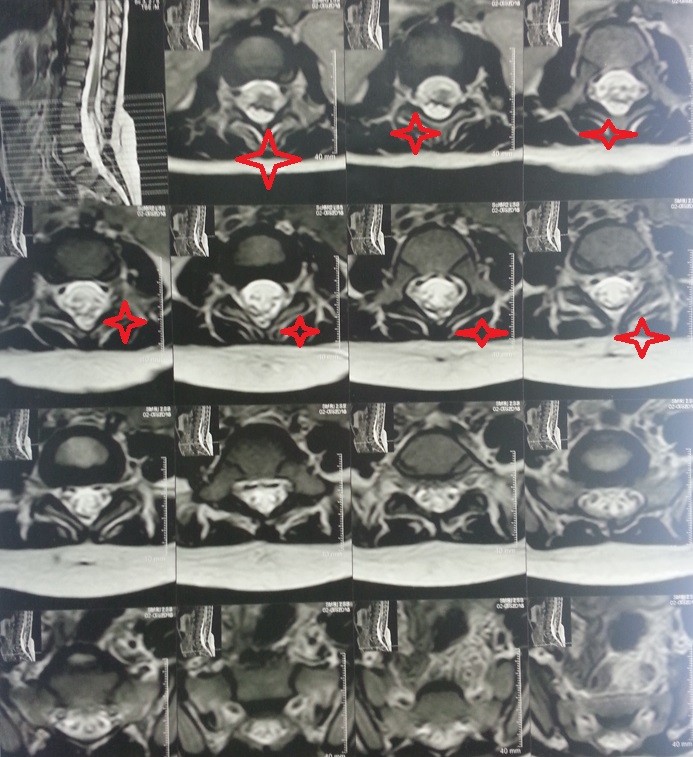

congenital fatty tumor of the spinal cord versus the lumbar vertebrae of a four-year-old girl